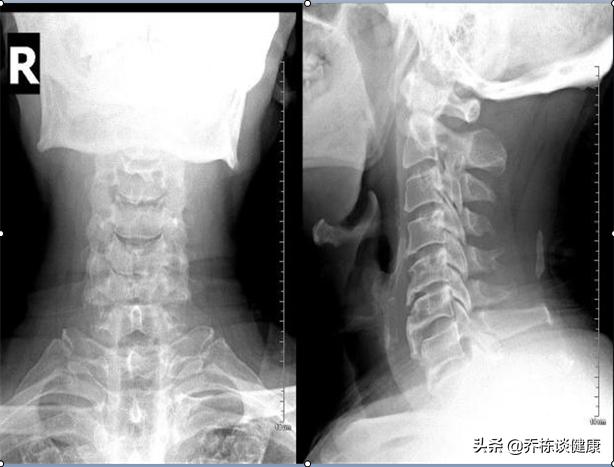

3.生理曲度反弓

之前说过,椎动脉和横突孔的位置关系,有的人生理曲度都反弓了,且很严重,这种人不用说,椎动脉的走向和供血就会有很大概率受到影响,诱发头晕的出现,因此,临床上不少人头晕,去拍片生理曲度反弓。